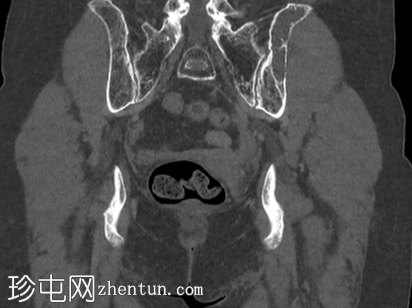

冠状位

骨窗

左侧髂骨内边界清晰的病灶

薄层硬化环

皮质变薄

轻微骨膨胀

内部密度低于肌肉和少量脂肪

薄骨间隔

无骨外软组织肿块

初步报告提示可能存在转移性疾病,因此进行了FDG PET/CT进一步评估。本例结果令人放心;SUV值可能与恶性

重叠。此外,MRI表现多样,病灶在T2加权序列上可呈高信号,并在注射钆后增强。

幸运的是,CT

表现为纤维性骨发育不良,属于不可触碰的病变。